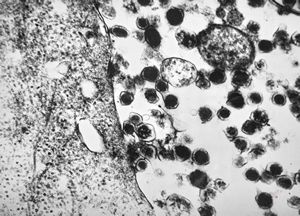

M, 63y. | suprarenal neuroblastoma

M, 3y. | suprarenal neuroblastoma